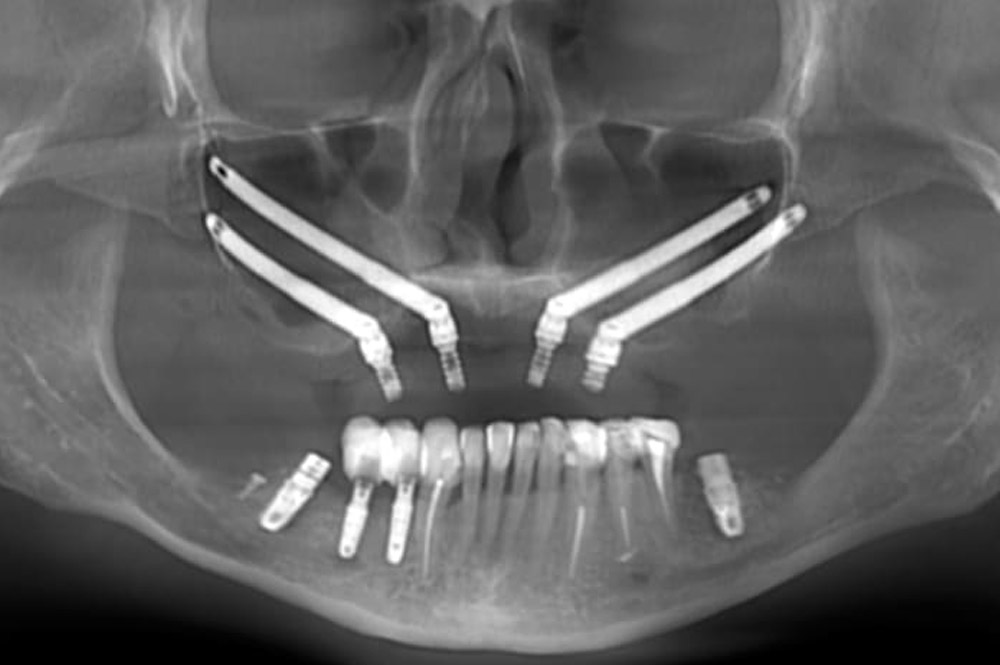

Implanty zygomatyczne są 3 do 5 razy dłuższe niż konwencjonalne. Umieszcza się je pod wyraźnym kątem. Cechy te pozwalają na ich zakotwiczenie w kościach jarzmowych (policzkowych), z ominięciem zatok szczękowych. Dzięki temu implanty zygomatyczne mogą być stosowane do rekonstrukcji górnych zębów, gdy jakość lub ilość kości szczęki jest zmniejszona. Leczenie przy użyciu implantów jarzmowych zostało po raz pierwszy zastosowane w końcu lat 80-tych ubiegłego wieku i, z pewnymi modyfikacjami, jest z powodzeniem wykorzystywane do dziś.

W celu zaplanowania leczenia z wykorzystaniem implantów jarzmowych wykonywana jest: tomografia komputerowa części twarzowej czaszki, konieczna do oceny warunków kostnych do wszczepienia implantów oraz wykluczenia schorzeń zatok szczękowych; analiza możliwości odbudowy protetycznej.